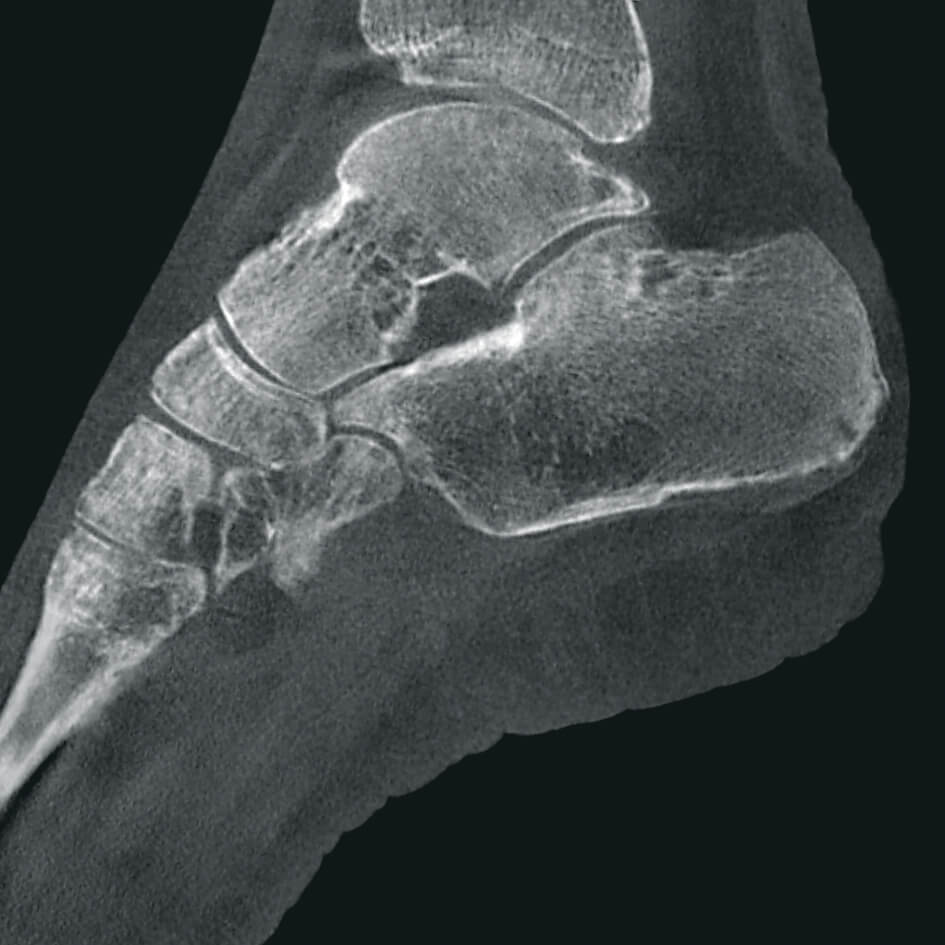

Полное отсутствие искажений снимков в сочетании с высоким динамическим диапазоном широко востребованы как при сложных операциях в нейрохирургии, сосудистой хирургии, инвазивной радиологии, так и в гибридных областях применения, а также в ортопедии, травматологии. В сосудистой хирургии особенно важны высокий динамический диапазон и пространственное разрешение, обеспечивающие детальную визуализацию даже мельчайших сосудов. Специализированное программное обеспечение SmartVascular позволяет проводить настройку системы для васкулярных операций и сосудистой хирургии.

Точная визуализация анатомических деталей, мягких тканей и костных структур обеспечивается за счет светочувствительной матрицы 3kх3k пикселей с высоким динамическим диапазоном.